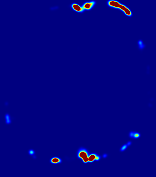

4.3.2 Diffusion Imaging via Advection-Diffusion

Slice #1Slice #2Slice #3Slice #4Slice #5Slice #6Dgtsuperscript𝐷gtD^{\text{gt}}Refer to captionRefer to captionRefer to captionRefer to captionRefer to captionRefer to captionDestsuperscript𝐷estD^{\text{est}}Refer to captionRefer to captionRefer to captionRefer to captionRefer to captionRefer to captionRefer to caption0.300.300.300.240.240.240.180.180.180.120.120.120.060.060.060.000.000.00(mm2/s)𝑚superscript𝑚2𝑠(mm^{2}/s)𝐕est𝟐subscriptnormsuperscript𝐕est2\|\bf{V}^{\text{est}}\|_{2}Refer to captionRefer to captionRefer to captionRefer to captionRefer to captionRefer to captionRefer to caption0.00300.00300.00300.00240.00240.00240.00180.00180.00180.00120.00120.00120.00060.00060.00060.00000.00000.0000(mm/s)𝑚𝑚𝑠(mm/s)

Figure 15: PIANO identifiability testing: diffusion imaging via advection-diffusion. Top row shows Dgtsuperscript𝐷gtD^{\text{gt}} used for simulating ground truth pure diffusion. Rows below show the estimated Destsuperscript𝐷estD^{\text{est}} and 𝐕est2subscriptnormsuperscript𝐕est2\|{\bf{V}}^{\text{est}}\|_{2} on corresponding slices. Note that the plotted value scale for 𝐕est2subscriptnormsuperscript𝐕est2\|{\bf{V}}^{\text{est}}\|_{2} is 0.01 of that for Dgtsuperscript𝐷gtD^{\text{gt}} and Destsuperscript𝐷estD^{\text{est}}.

Similarly, we test the behavior of PIANO when estimating both advection and diffusion from a pure diffusion-driven process. The goal is to determine if PIANO is able to recognize that there is only diffusion governing the given concentration time-series. We use the same ‘Diffusion Imaging’ data simulation of Sec. 4.2.1 as the concentration dataset, PIANO estimates both velocity 𝐕estsuperscript𝐕est{\bf{V}}^{\text{est}} and diffusivity Destsuperscript𝐷estD^{\text{est}}. Estimation results in Fig. 15 confirm PIANO’s identifiability again: the estimated 𝐕est2subscriptnormsuperscript𝐕est2\|{\bf{V}}^{\text{est}}\|_{2} is almost invisible compared to Destsuperscript𝐷estD^{\text{est}}, even plotted with a 1%percent11\% value range compared to that for Destsuperscript𝐷estD^{\text{est}}. On the other hand, Destsuperscript𝐷estD^{\text{est}} achieves comparable estimation performance as ‘Diffusion Imaging via Diffusion’ in which PIANO predicts Destsuperscript𝐷estD^{\text{est}} alone (shown in Fig. 13).